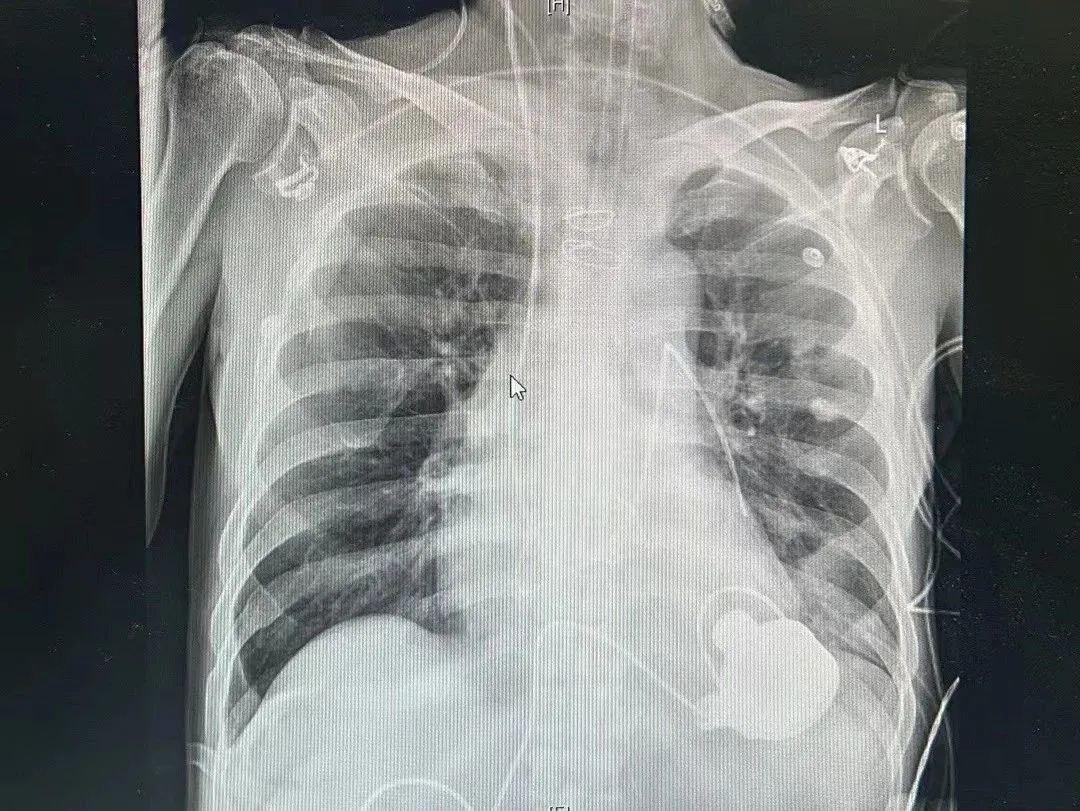

直到他出现了严重的胸闷憋气的心衰症状,明显面颊暗红、口唇紫绀,才来到医院就诊。2023年9月21日老杨被收入北京大学第三医院心血管内科病房。

超声心动的结果极不乐观,二尖瓣极重度反流,射血分数只有30%,老杨出现严重的心力衰竭,且左心室已经扩大到了80mm,几乎是正常人的两倍。雪上加霜的是,老杨还有严重的肾功能不全,只有通过血液透析才能把体内多余的水分排出去,这对于心衰的治疗更增加了一分难度。

心衰的病因不解除,老杨的症状就无法得到缓解,因为急性左心衰造成呼吸困难,老杨不得不在术前就进行气管插管辅助呼吸。而且,患者脆弱不堪的心脏功能也经受不起外科换瓣手术。